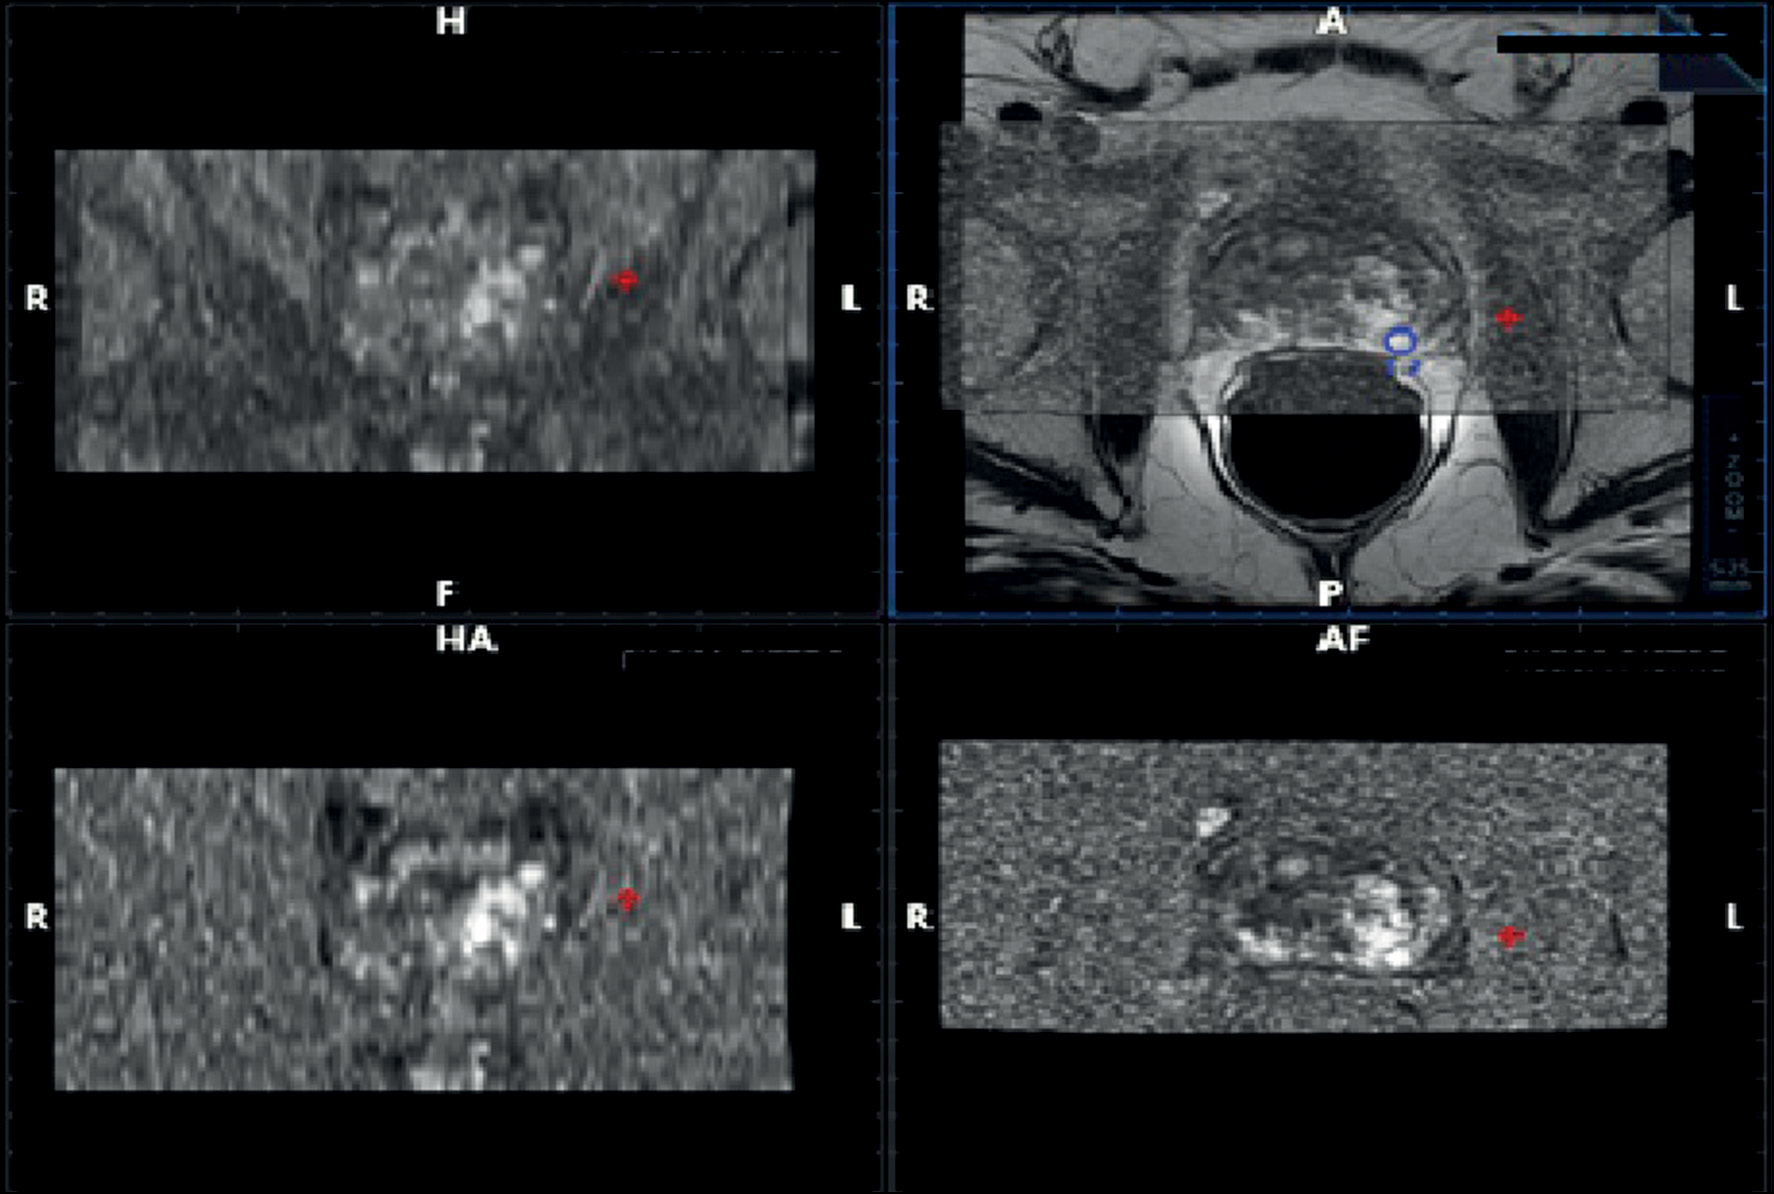

Fig. 1. T2-weighted (a) magnetic resonance image (axial plane) showing a hypointense nodular lesion in the peripheral zone at the apical posterior site. Axial diffusion-weighted MR image (b) with an apparent diffusion coefficient (ADC) (c) of put value × 10−3 m2/sec in the corresponding area. Reduced water diffusion in prostate cancer (PCa) is related to increased cellularity of malignant lesions, with a reduction in the extracellular space and restriction of movement of a larger portion of water molecules into the intracellular space. Therefore, DWI with the corresponding ADC map provides an important quantitative biophysical parameter that can be used to diagnose PCa (d). The tumor is characterized by intense early hyperenhancement of the normal adjacent tissue (e). Colorimetric map generated by the DCE evaluation of PCa in the peripheral area at the apical site. The suspicious area is coded in red (f).

Fig. 3. Magnetic resonance (MR) imaging of prostate cancer: axial diffusion-weighted MR image (up on the left) with an apparent diffusion coefficient map (down on the left), T2-weighted MRI image (up on the right), and T1-weighted image after contrast media (down on the right).